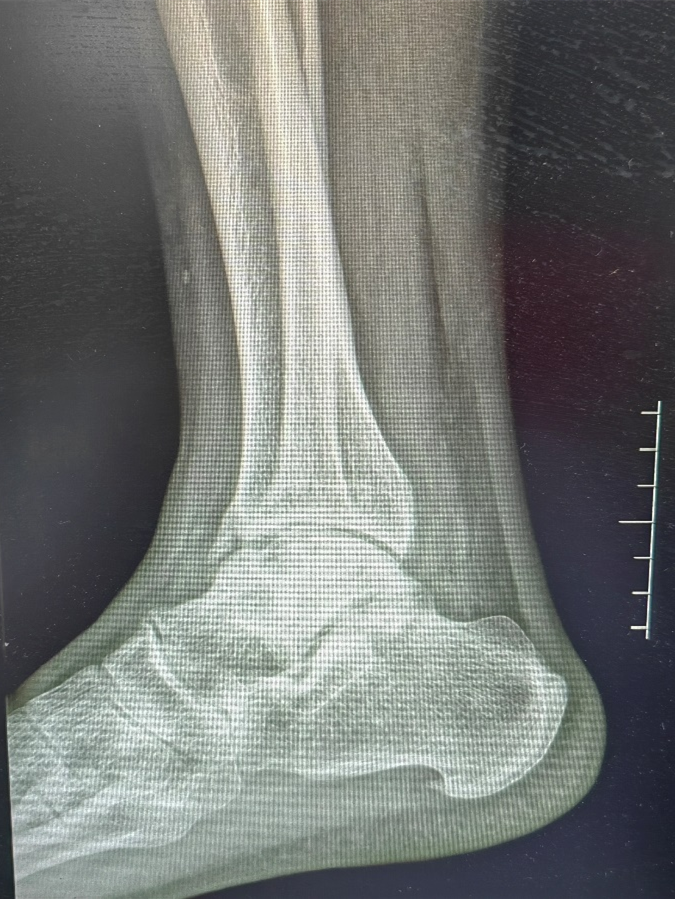

X线检查可见患者出现右踝关节退变,距骨坏死